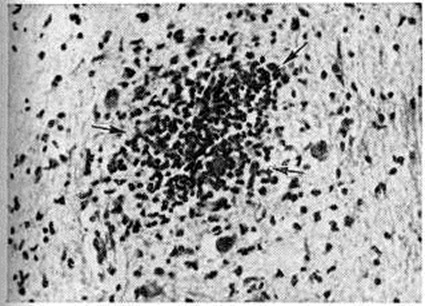

В головном мозге (смотри полный свод знаний) сыпнотифозные узелки, впервые описанные Л. В. Поповым (1875), обнаруживаются в варолиевом мосту (мост головного мозга), ножках мозга, коре головного мозга, базальных ядрах, таламусах (зрительных буграх), мозжечке, гипоталамусе, задней доле гипофиза. Как правило, сыпнотифозных узелков нет в белом веществе полушарий головного мозга. Сыпнотифозные узелки в ткани головного мозга построены из клеток микроглии, к к-рым, как правило, примешиваются сегментоядерные лейкоциты (рисунок 1). Важное диагностическое значение имеет скопление сыпнотифозных узелков в продолговатом мозге, в частности в области его нижних оливных ядер. Количество таких узелков в центральная нервная система зависит в основном от длительности лихорадочного периода. В случае смерти на 2—4-й неделе болезни их обнаруживают в 100%. У переболевших сыпнотифозные узелки регрессируют. Сохраняющиеся в более поздние периоды болезни гистологические изменения могут быть диагностическим признаком перенесённого в прошлом Сыпной тиф эпидемический

Рис. 1.

Микропрепарат головного мозга при сыпном тифе: стрелками указан сформированный сыпнотифозный узелок, состоящий из клеток микроглии и сегментоядерных лейкоцитов; окраска гематоксилин-эозином; ×120.